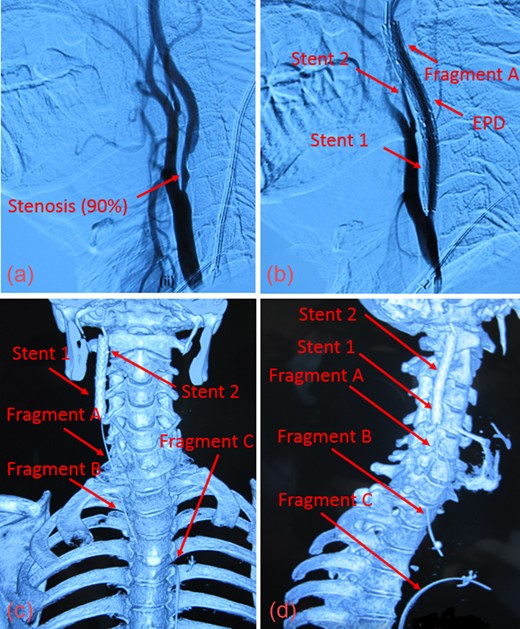

Upon presentation, we found moderate (55%) stenosis in the right common carotid artery (CCA) and severe (90%) stenosis in the ICA inferior to Stent 1. The most superior of the three guidewire fragments (Fragment A), still attached to the EPD, was compressed by Stent 2 and extended into the CCA (Fig. 1c and d). The middle piece (Fragment B) was adhered to the right CCA wall by local fibrin deposits. The inferior fragment (Fragment C) extended from the right femoral artery to the thoracic aorta, where it punctured the proximal aortic arch wall (Fig. 2a and b). Thrombus had also formed along the entire 1-meter length of Fragment C.

(a) The inferior aspect of Fragment C extended down to the femoral artery. (b) The superior aspect of Fragment C penetrated the thoracic aorta.